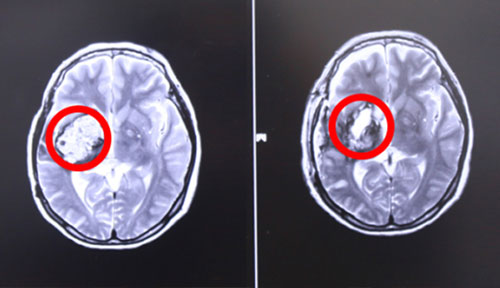

左侧为术前,右侧为术后,术后红圈内肿瘤物基本消失

17号上午9点左右,张XX被推入手术室,在全麻状态下接受“右颞顶海绵状血管瘤切除术”。至手术结束,已经日暮时分。手术由经验丰富的侯增欣主任主刀,上显微镜,分离侧裂,保护血管,切开颞上回皮质,见肿物呈暗褐色,靠近侧裂动脉,并向大脑深部丘脑生长,术中显微镜下肿物近全切除,手术顺利,脑神经及血管保护完好,患者全麻醒,返ICU病房进行术后监护。